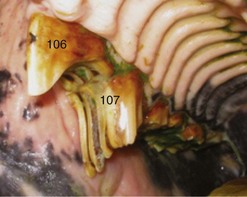

Classically, the loss of a cheek tooth is alleged to cause a rectangular shaped overgrowth due to ‘super-eruption’ of the unopposed opposite CT, leading to a condition termed step mouth (Fig. 10.3). Dixon et al13 found that 40 % of cases of step mouth were caused by CT maleruptions, such as different rates of eruption of opposing CT, with the earlier erupted CT becoming and remaining overgrown (’dominant’).17,22 As noted above, less severe cases of CT maleruption may lead to wave mouth and there is often an overlap between these two disorders. Overgrown teeth may be rectangular in shape, especially in the early stages following loss of an opposite tooth, but as the teeth on either side of the missing tooth (variably) drift together, a triangular-shaped overgrowth can develop (Fig. 10.4).31 These overgrowths can mechanically interfere with normal mastication, leading to wave mouth or shear mouth. They may also cause oral pain that may be manifested as oral pain with quidding, halitosis, and weight loss.28

image

Fig. 10.4 These two major maxillary CT overgrowths have been caused by loss of the opposite 407, with marked caudal drifting of the 406 into the extraction space. This has caused a rostral overgrowth to develop on the partly unopposed 106, and a tall, narrow, triangular overgrowth to develop on the 107.